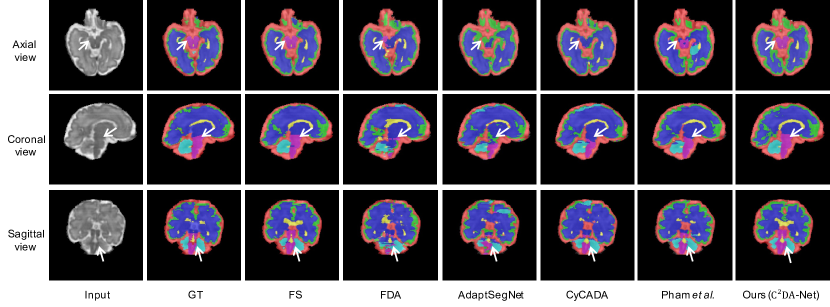

Refer to caption

Figure 8: Qualitative results of the ablation study in two samples. The last five columns correspond to the five controlled experiments in Table 3.

4.4 Ablation Study

There are four key components in our method, including 1) registration for source data, 2) FCC extraction, 3) the generator and 3) discriminator for adversarial learning in the segmentor. As the FSC is a critical component of the generator, and without it, the synthesis would not be valid, we consider the FSC to be a necessary ingredient of the generator. To validate the effectiveness of the different components proposed in our method, we design the following ablated versions of our method:

• Reg: This ablated version only has a segmentor trained on the registered source images which are described in Section 3.1 and directly applies the trained model to the target data for segmentation.

• Reg-FCC: In this ablated version, we augment the Reg with the FCC, so that the segmentor takes the FCC of registered source images as input and applies the trained model to the FCC of target data for segmentation.

• Reg-G: This ablated version augments the Reg with a generator, and the segmentor takes the registered source images and target images as input. The generator accepts the combination of prediction and the corresponding FSC as input to synthesize the original image. Note that the generator is discarded during the testing stage.

• Reg-FCC-G: We augment the Reg-G with the FCC in this ablated version. The segmentor takes the FCC of registered source and target data as input.

• C2DA-Net (Reg-FCC-G-Adv): This is the full version of our method, which combines all the four key components together.

We also include the low bound (i.e., WoDA in Section 4.2) for better evaluation of different ablated versions.

4.4.4 Effectiveness of Adversarial Training

Adversarial learning is a powerful technique that we use in C2DA-Net to align the features extracted from source and target domain data. This technique has been demonstrated to be effective in various studies [12, 16, 11, 10, 14] and our results in Table 3 and Fig. 8 confirm its effectiveness in our method.